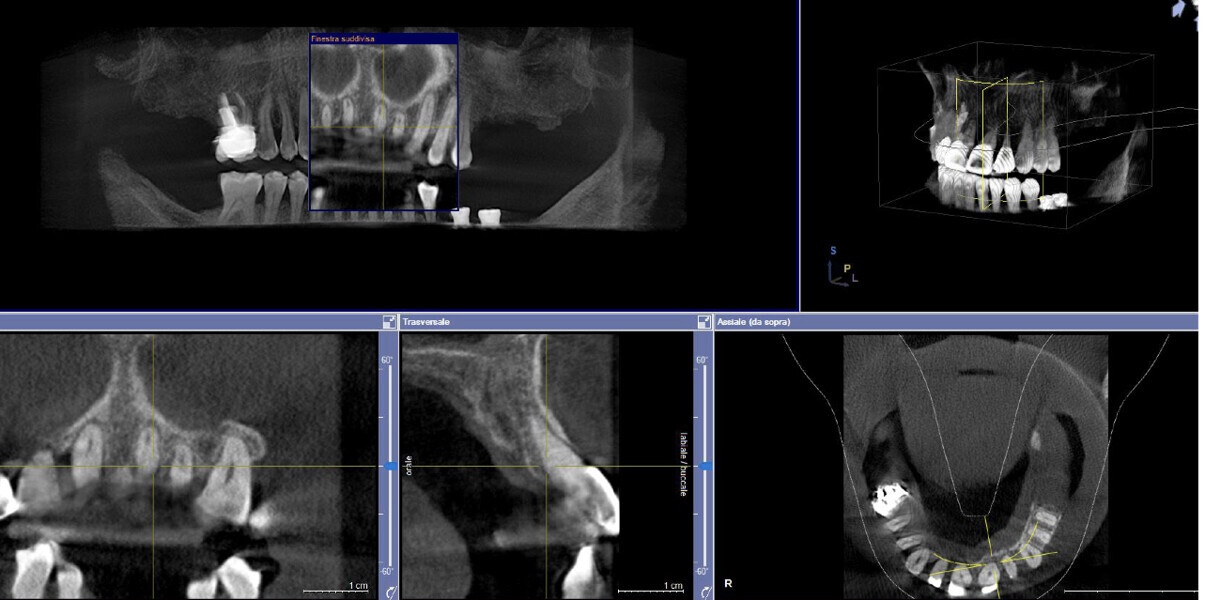

This patient, like all patients requiring interdisciplinary rehabilitation, had to first undergo periodontal treatment and caries restoration (Fig. 17). At the same time, it was important to rehabilitate swallowing with Froggymouth and relax the masticatory muscles and relieve the TMJs with an occlusal device. We could then study the orthodontic treatment plan using Invisalign ClinCheck (Align Technology) and showed the treatment plan to the interdisciplinary team and to the patient (Fig. 18). We were then able to create the correct sequence of orthodontic treatment, bone augmentation and implant surgery needed for the posterior edentulous spaces.

After the first phase of aligner treatment, we had achieved better inter-arch coherence, better maxillary arch expansion, and some space for improving the anterior tooth proportions restoratively (Fig. 19). We then temporarily restored the anterior teeth directly with composite, closing the spaces, improving the tooth proportions and further increasing the maxillary arch expansion (Fig. 20). We used restorative arch expansion to reduce the orthodontic destabilisation of the teeth to achieve the correct inter-arch coherence and retain the teeth in the cortical bone.38 A refinement aligner phase was undertaken to improve the final alignment of the gingival zenith and to improve the inter-arch coherence (Fig. 21). The periods of the first orthodontic phase and of the refinement were used to augment the mandibular and maxillary bone and to place the implants (Fig. 22). At the end of the orthodontic treatment, the case was finalised with ceramic veneers in the anterior area and temporary restorations on the implants in the posterior area (Figs. 23–26).